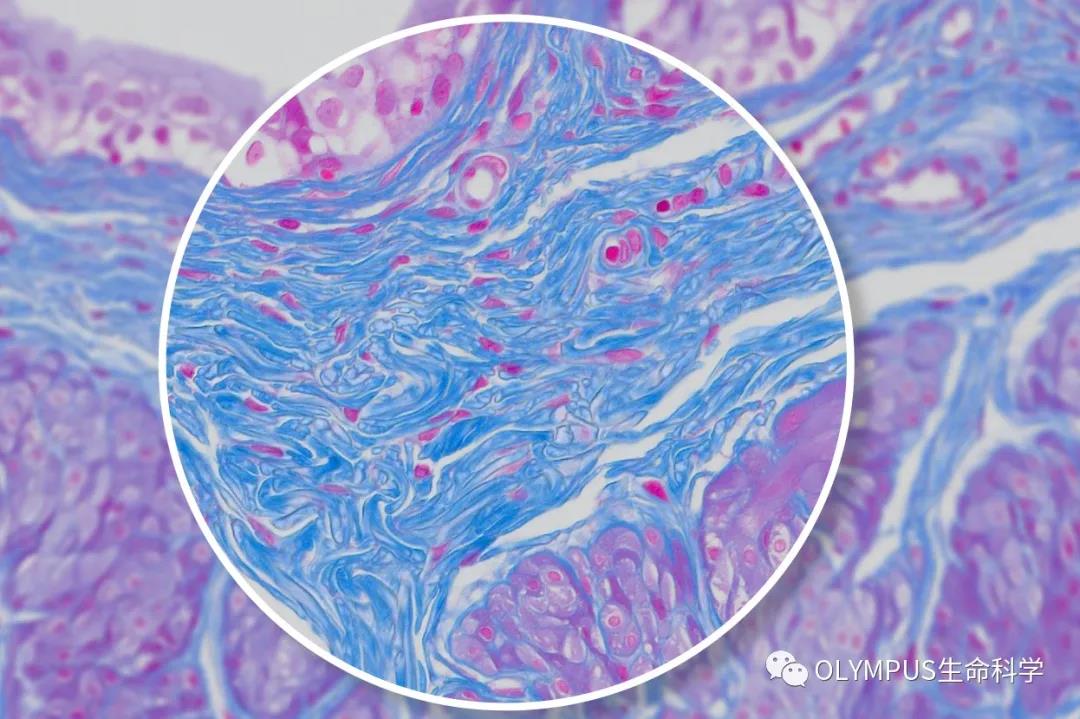

具备4K超高清图像质量的DP28相机让用户能够共享和讨论样品图像的细微之处,而具备640万像素分辨率和每秒45帧速率的DP23相机则能够轻松快速捕捉满足大多数生命科学成像应用细节所要求的图像。

在显示器或大屏幕上显示显微图像时,尽可能高的分辨率以及更快的帧率非常重要。DP28相机的890万像素CMOS图像传感器、全局快门以及4K分辨率(每秒32帧)能够提供出色图像质量。为了捕捉到快速移动样品的流畅图像,相机能够以64 fps采集与标准显示器最大帧率匹配的全高清实时图像。

与DP系列的所有相机一样,这两款相机均能够准确还原色彩,让染色标本看起来与预期别无二致。